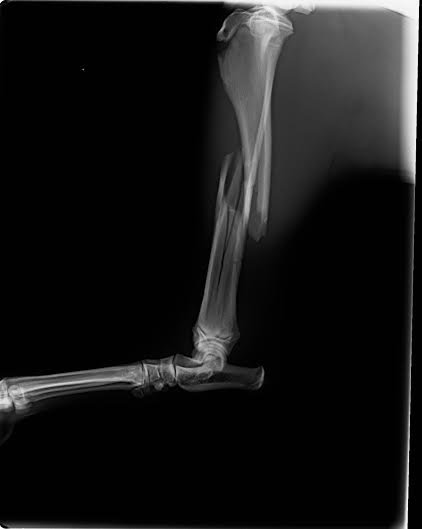

A törött lába olyan súlyosan sérült, hogy teljesen benyomódott a medencéjébe, így őt is combcsontfejezni kellett. Kísérteties hasonlóság, hö? Jó, neki van még egy implanizével összerakott félbetört alsó lábszára is, de ez tökre részletkérdés, a szőrszálhasogatás meg megöli a romantikát.